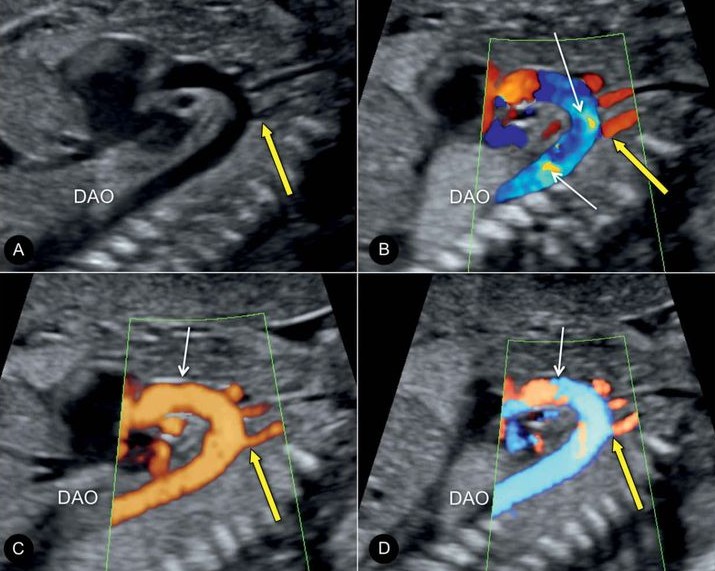

Color Doppler Study

USG in Pregnancy